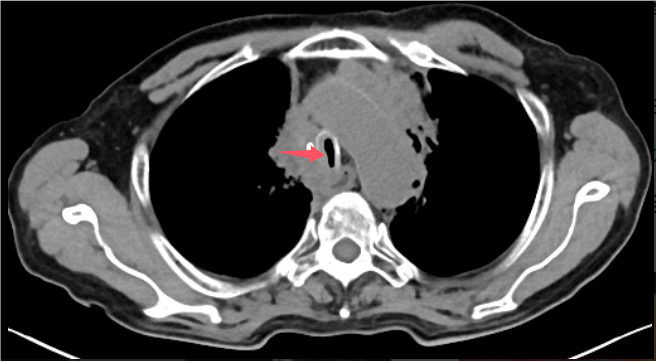

近日,重庆医科大学附属璧山医院(重庆市璧山区人民医院)胸心血管外科团队成功实施我院首例经右胸小切口心脏不停跳下心脏微创手术。该术式突破传统开胸方式,以微创技术实现精准修复,标志着我院在微创心脏病外科治疗领域迈上新台阶。